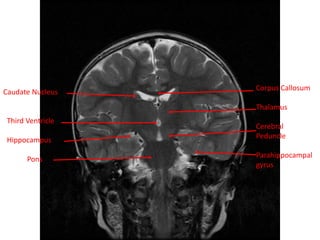

Caudate Nucleus

Third Ventricle

Hippocampus

Pons

Corpus Callosum

Thalamus

Cerebral

Peduncle

Parahippocampal

gyrus

Caudate Nucleus Third Ventricle Hippocampus Pons CorpusCallosum Thalamus Cerebral Peduncle Parahippocampal gyrus